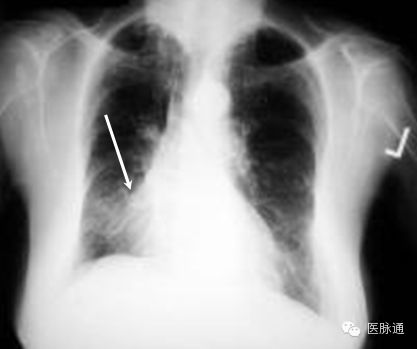

张力性气胸是指空气蓄积于胸膜腔内。当受损肺组织形成单向活瓣,造成空气只能进入而无法离开胸膜腔,即形成张力性气胸。应根据临床表现作出张力性气胸的诊断,包括气管向对侧移位,同侧叩诊过清音,同侧呼吸音降低,颈静脉充盈以及低灌注。典型的X线表现包括同侧肺塌陷(图3白色箭头)伴肋间隙增宽,以及纵隔向对侧移位(图3红色箭头)。若张力性气胸发生于左侧,则左侧膈肌下降,但若发生于右侧,则肝脏可限制膈肌的下降。

图3